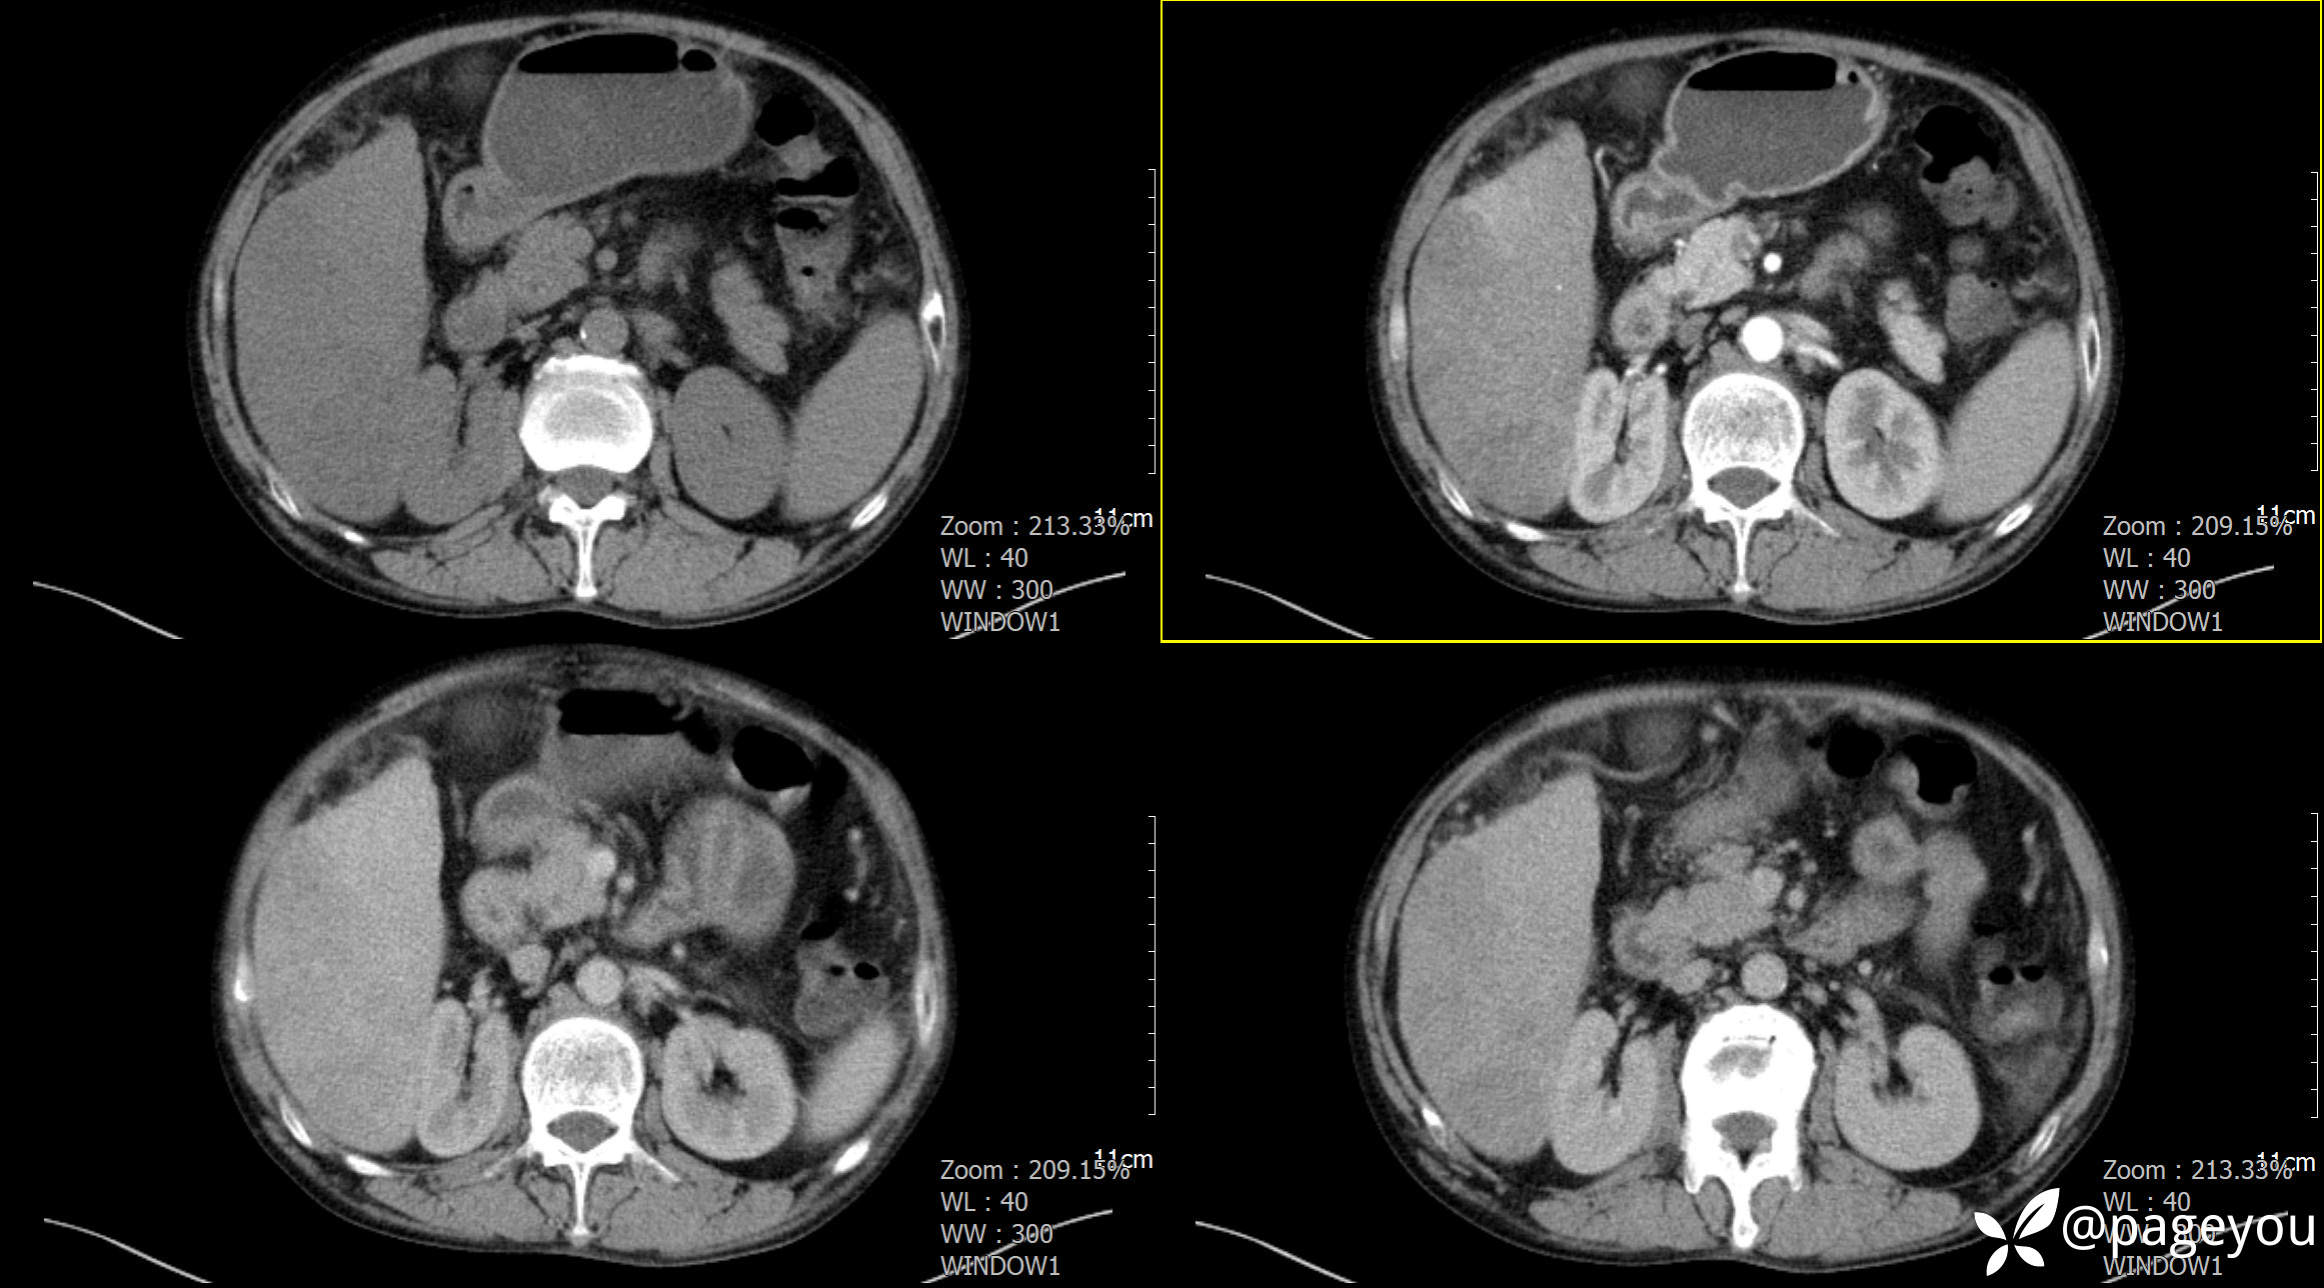

CT检查: